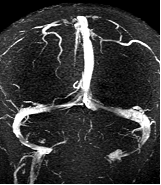

1.4 磁共振成像MRI

1946年美国Stanford大学 Felix Bloch和Harvard大学的 Edward Purcell各自独立行磁共振现象研究,1952年他们荣获诺贝尔物理学奖。MRI应用逐渐扩展,在医学诊断中被认为是最重要的进展。

MR是一种生物磁自旋成像技术,它是利用原子核自旋运动的特点,在外加磁场内,经射频脉冲激后产生信号,用探测器检测并输入计算机,经过计算机处理转换后在屏幕上显示图像。